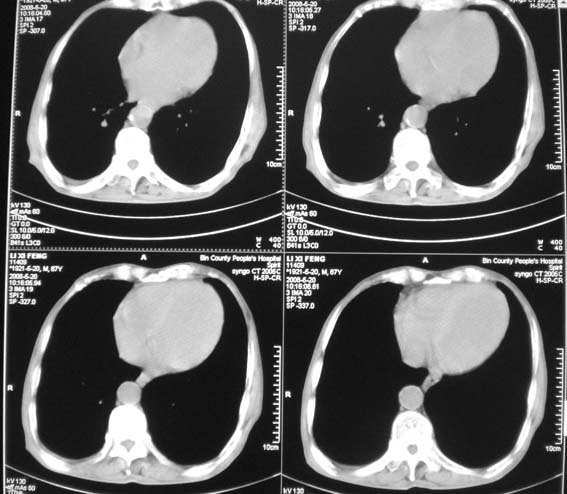

男,87岁,咳嗽、发烧、有黄痰,胸片示肺结核。

考虑继发型结核伴右上霉菌球形成。

继发性肺结核,真菌感染,不出外占位性病变,建议治疗后复查

右肺上叶尖后段片状不规则致密影,密度欠均匀,相邻胸膜肥厚,纵隔内见多发肿大、钙化淋巴结,考虑为结核,部分坏死